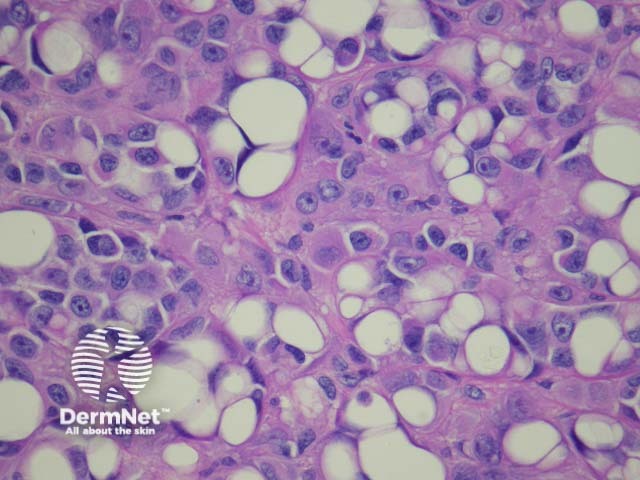

Cutaneous metastasis of melanoma can cause diagnostic confusion. The metastatic melanoma may invade the dermis or subcutis and form a nodular tumour mass without invasion of the overlying epidermis (figure 1). The pattern of growth may mimic a benign intradermal naevus at low power (figure 1) but at high power examination the nuclear atypia is usually obvious, there may be mitoses and there is minimal evidence of maturation (decrease in cell size) with descent in the dermis (figure 2). Usually the lack of epidermal involvement is a good clue the tumour is a metastasis from another site but sometimes the metastasis may invade the epidermis and closely simulate a primary melanoma.

Rarely, melanoma which has metastasised to the dermis may closely mimic a blue naevus (blue naevus-like melanoma, figures 3,4). This can cause considerable diagnostic difficulty and be impossible to correctly recognise without clinical information.

Figure 1

Figure 2

Figure 3

Figure 4